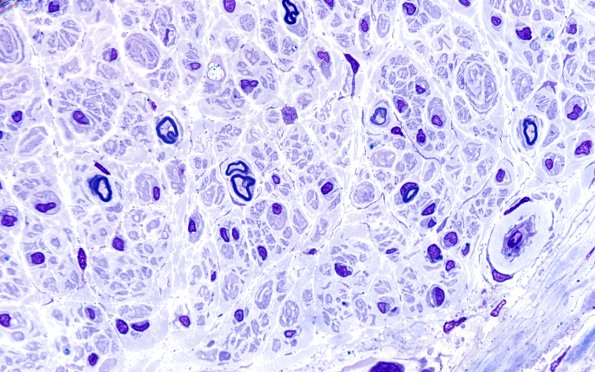

Washington University Experience | PERIPHERAL NEUROPATHY | 7A GUILLAIN-BARRE SYNDROME (GBS) | 10A2 (Case 10) 100X sp GBS. 2

A few relatively large axons without myelin sheaths are noted which are intimately associated with macrophages carrying myelin debris consistent with an active, macrophage mediated demyelination. There is a hint of onion bulb or pseudo-onion bulb formation, suggesting the possibility of CIDP. ---- Not shown: which are intimately associated with macrophages carrying myelin debris consistent with an active, macrophage mediated demyelination. Macrophage mediated demyelination is a pathologic process typically associated with CIDP and Guillain-Barre syndrome.